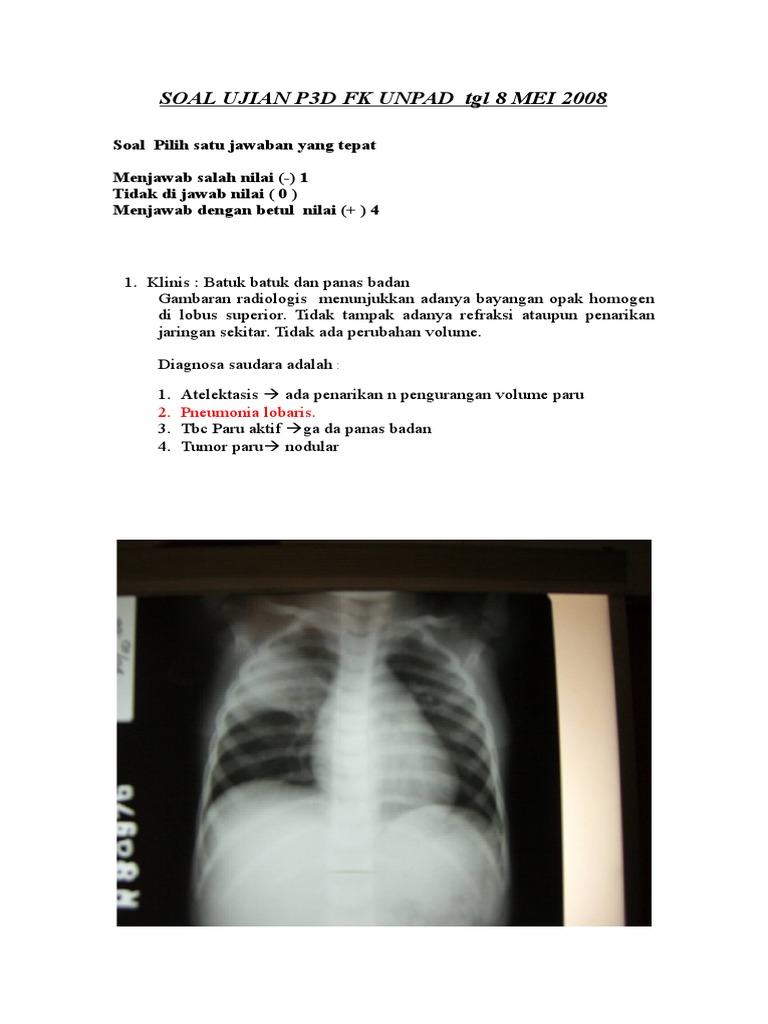

Kumpulan Soal Radiologi Xliiib Diunggah oleh azizahputri Soal Test Masuk Radiologi Diunggah oleh windipijiastuti Kunci Jawaban Soal Tes Seleksi Radiologi Diunggah oleh diasayu SOAL TRYOUT UKOM D3 16 JUNI 2017-180. Download View Kumpulan Soal Radiologi Xliiib as PDF for free.

Contoh Soal Ujian Tulis Seleksi Ppds Radiologi

Kumpulan Materi Radiologi Tuesday 5 March 2013 KUMPULAN SOAL-SOAL 1. Soal Pilihan Ganda Radiologi Lengkap dengan Jawaban Edisi 48 Contoh UKOM radiografer 2020 2021 pdf Edisi 47 Latihan Soal UKOM Radiografer dan Jawaban 2020 2021 Edisi 46. Prol Tape Kue Icon android.